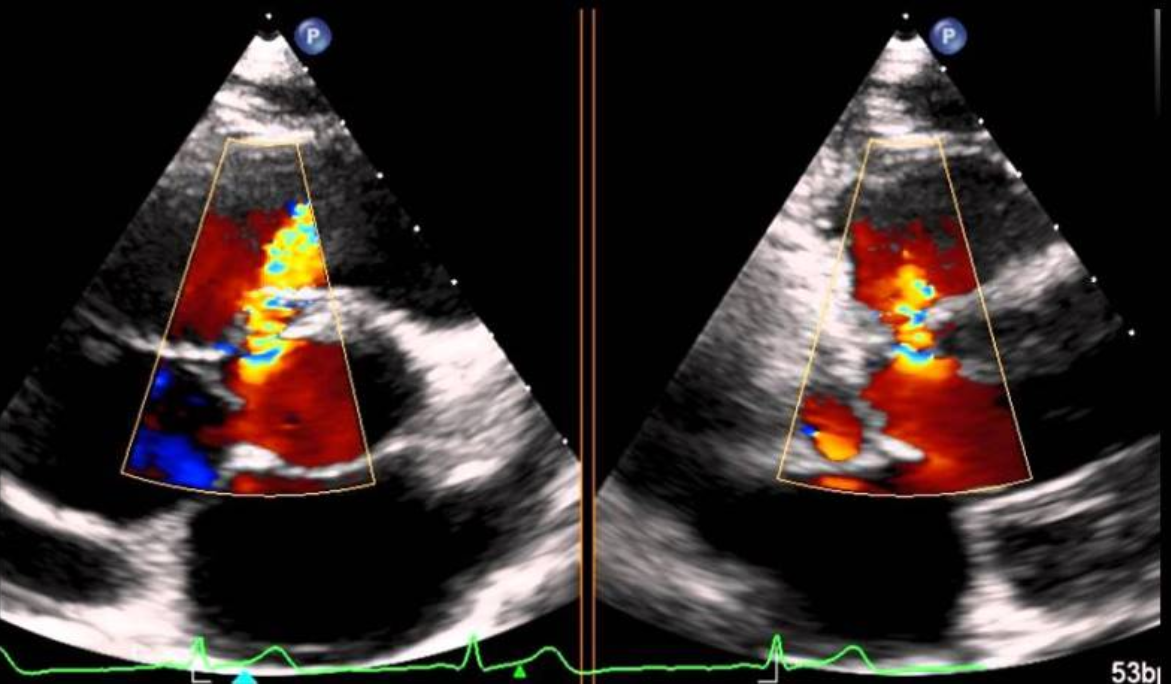

Un ultrasonido expone la región de interés del cuerpo a ondas sonoras de alta frecuencia. Las imágenes del ultrasonido son capturadas en tiempo real; eso es, no sólo muestran la estructura de una parte en particular del cuerpo, sino que también pueden mostrar el movimiento de los órganos internos así como el flujo de sangre a través de los vasos. Ultrasonido Doppler, es una aplicación especial del ultrasonido que mide la dirección y velocidad de las células sanguíneas a medida que se mueven por los vasos. El movimiento de las células sanguíneas causa un cambio en el tono de las ondas acústicas reflejadas, denominado efecto Doppler. Una computadora recopila y procesa los sonidos y crea gráficos o imágenes a color que representan el flujo sanguíneo a través de los vasos sanguíneos.